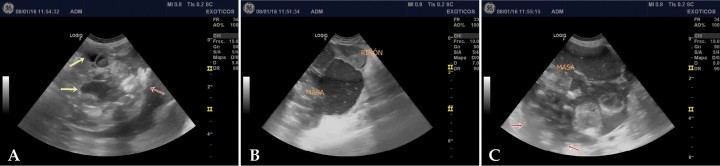

Se realizaron radiografías de abdomen, lateral y ventrodorsal (Fig. 1). En ambas proyecciones fue evidente la presencia de una masa que ocupaba prácticamente la totalidad del abdomen, lateralizada levemente hacia la izquierda. Dicha masa presentaba una opacidad tejido blando, con pequeñas áreas mineralizadas. Asimismo, existía una cantidad moderada de gas en asas intestinales.

<p>Radiografías de abdomen. (A) Proyección laterolateral. (B) Proyección ventrodorsal. Se observa la presencia de una masa (flechas negras) ocupando el abdomen casi en su totalidad y lateralizada hacia la izquierda. Se aprecian zonas de opacidad hueso (flechas rojas) en el interior de la masa. En intestino se observan zonas de opacidad gas (flechas amarillas).</p>

Radiografías de abdomen. (A) Proyección laterolateral. (B) Proyección ventrodorsal. Se observa la presencia de una masa (flechas negras) ocupando el abdomen casi en su totalidad y lateralizada hacia la izquierda. Se aprecian zonas de opacidad hueso (flechas rojas) en el interior de la masa. En intestino se observan zonas de opacidad gas (flechas amarillas).